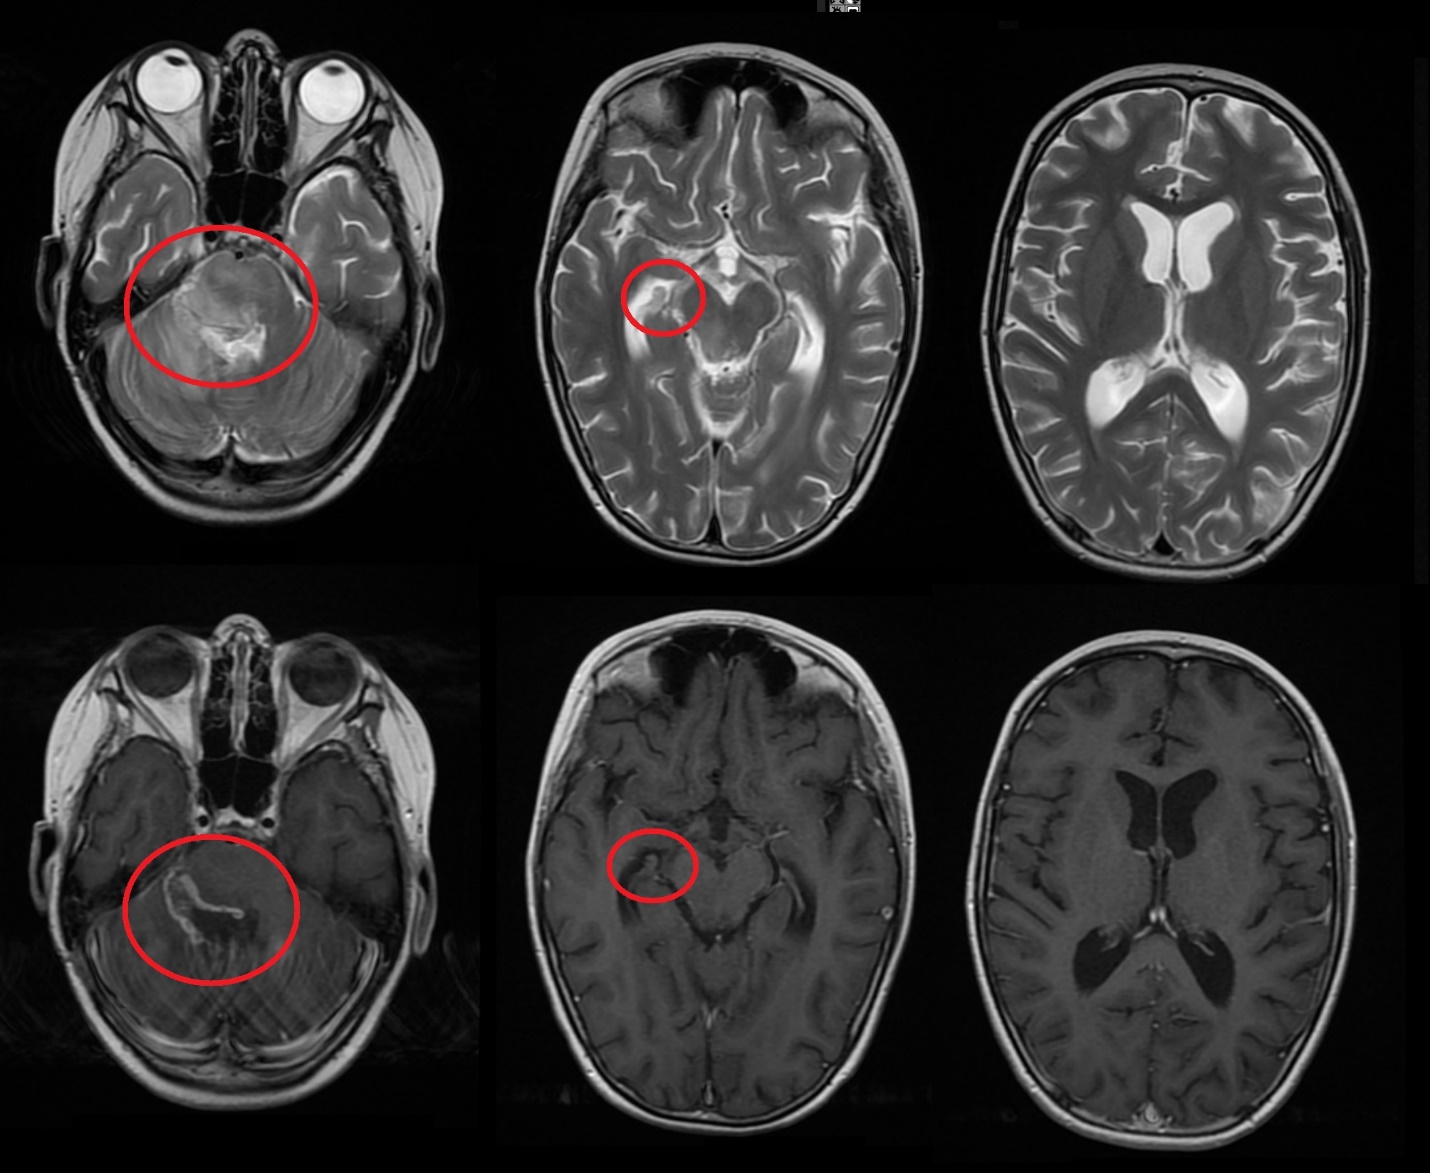

Результаты. У 19 пациентов (50 % от 38 прошедших биопсию) по данным иммуногистохимического анализа послеоперационного материала была выявлена мутация К27М в гене H3F3A. У 6 (15 %) пациентов из 38 МРТ в сроки от 2 до 5 мес (медиана – 4,5 мес) после окончания лучевой терапии выявлено нехарактерное прогрессирование ДСГ в виде метастазирования по желудочковой системе головного мозга. У остальных пациентов когорты исследования, не проходивших процедуру биопсии, подобный характер прогрессирования не наблюдался (p<0,002): у них, как правило, отмечался продолженный рост опухоли (n=96), у 4 больных диагностировано лептоменингеальное метастазирование по спинному мозгу.

Заключение. Нами выявлены случаи нетипичного прогрессирования ДСГ в виде метастазирования по желудочковой системе у детей после открытой биопсии опухоли. Есть основания полагать, что биопсия могла способствовать диссеминации ДСГ по ликворным пространствам. Необходим поиск альтернативных методов оценки молекулярно-генетических характеристик ДСГ.